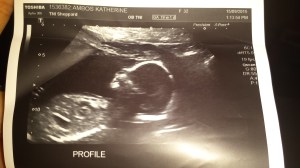

So when Mommy and Daddy brought home pictures of baby #2 today she was very happy. She blew the pictures kisses and said “Hi baby!” Madison stayed home with Nana so she could have her nap and lunch while Mommy and Daddy went to see baby #2. The gender was seen and Madison will be revealing it with the help of her Aunt Nadia on Saturday! ….stay tuned.

Baby #2